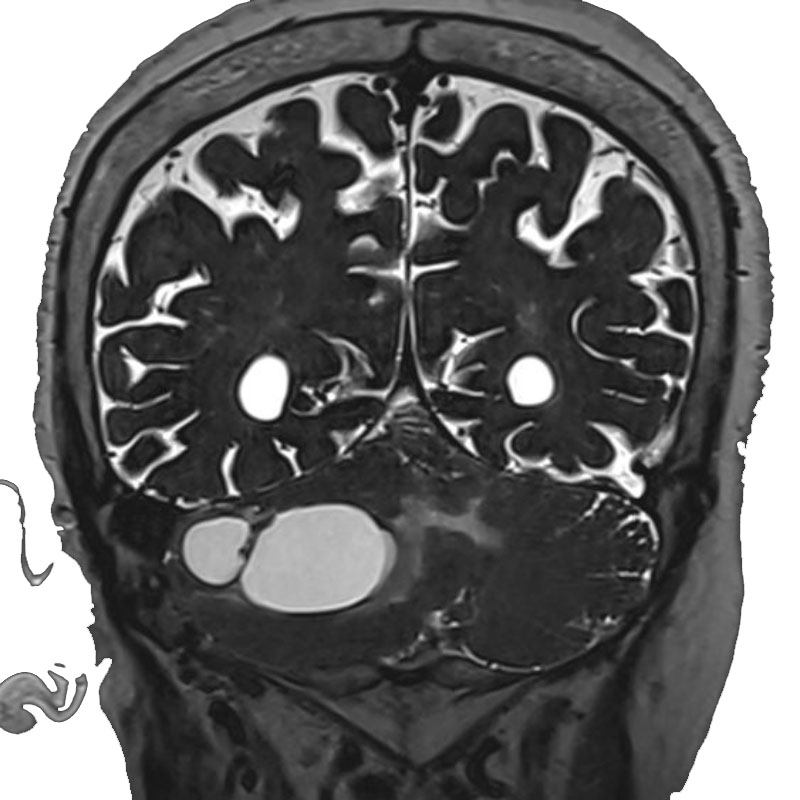

脳室内腫瘍

摘出術

北野/濵田